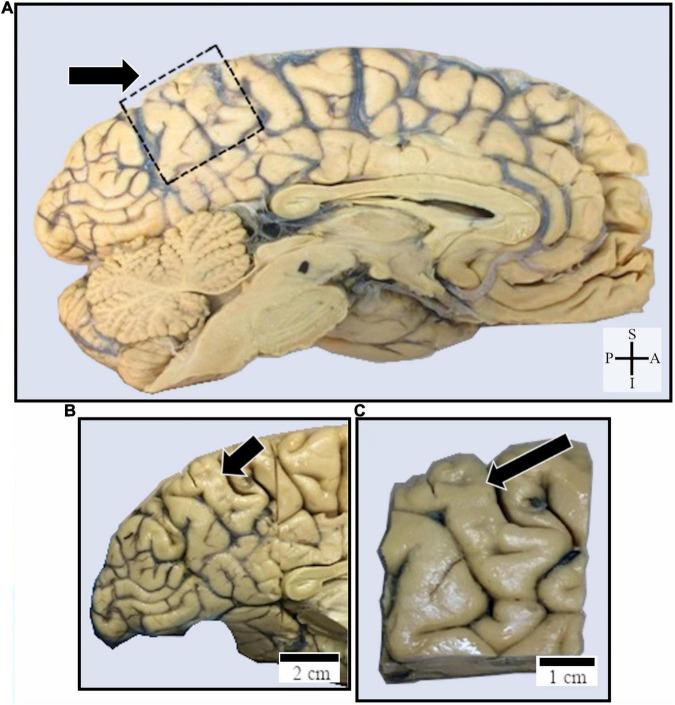

The human posteromedial cortex (PMC), which includes the precuneus (PC), represents a multimodal brain area implicated in emotion, conscious awareness, spatial cognition, and social behavior. Here, we describe the presence of Nissl-stained elongated spindle-shaped neurons (suggestive of von Economo neurons, VENs) in the cortical layer V of the anterior and central PC of adult humans. The adapted "single-section" Golgi method for postmortem tissue was used to study these neurons close to pyramidal ones in layer V until merging with layer VI polymorphic cells. From three-dimensional (3D) reconstructed images, we describe the cell body, two main longitudinally oriented ascending and descending dendrites as well as the occurrence of spines from proximal to distal segments. The primary dendritic shafts give rise to thin collateral branches with a radial orientation, and pleomorphic spines were observed with a sparse to moderate density along the dendritic length. Other spindle-shaped cells were observed with straight dendritic shafts and rare branches or with an axon emerging from the soma. We discuss the morphology of these cells and those considered VENs in cortical areas forming integrated brain networks for higher-order activities. The presence of spindle-shaped neurons and the current discussion on the morphology of putative VENs address the need for an in-depth neurochemical and transcriptomic characterization of the PC cytoarchitecture. These findings would include these spindle-shaped cells in the synaptic and information processing by the default mode network and for general intelligence in healthy individuals and in neuropsychiatric disorders involving the PC in the context of the PMC functioning.